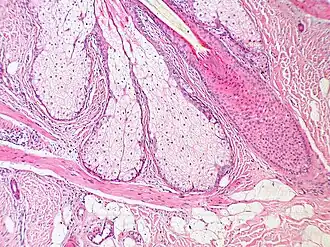

De musculus arrector pili[2] (meervoud: musculi arrectores pilorum) of haaroprichter[1] is een kleine spier bestaand uit glad spierweefsel die zich bij elke haarwortel bevindt van zoogdieren. Het is een onwillekeurige spier die de mogelijkheid biedt om onze haren rechtovereind te zetten (kippenvel). Als deze spier zich aanspant, gaan onze haren rechtovereind staan.

De haren worden altijd onder een bepaalde hoek ingepland. De musculus arrector pili is altijd terug te vinden aan de stompe hoek. Zo is het principe van thermoregulatie verder te verklaren: reflexmatig wordt de spier gecontraheerd waardoor de volledige haarfollikel tezamen met het haartje recht wordt getrokken. Hierdoor wordt de stilstaande lucht dat tussen de haren zit iets dikker. Hoe dikker de stilstaande lucht, hoe beter de isolatie.